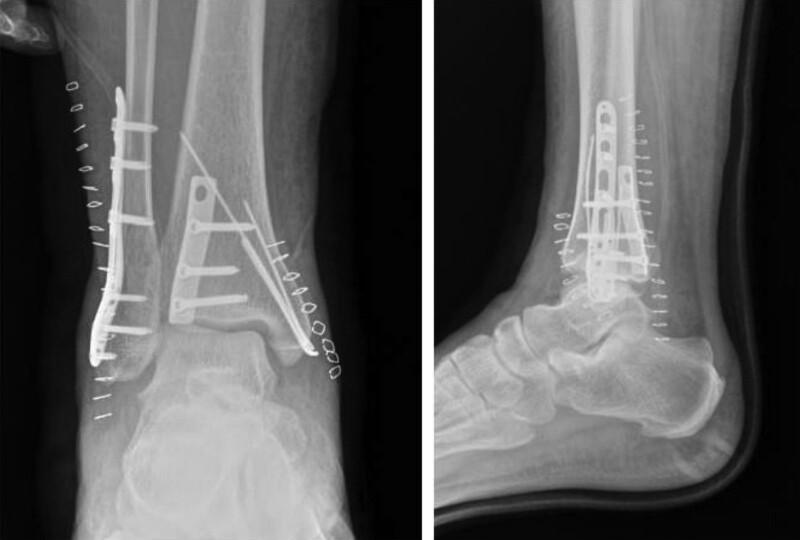

The patient was diagnosed with trimalleolar fracture accompanying ankle dislocation initially. We missed the diagnosis of accompanied deltoid ligament due to the arthralgia of medial ankle and the widened medial articular space in X-ray after operation.

As we missed the diagnosis of accompanied deltoid ligament, we only selected open reduction and internal fixation for trimalleolar fracture at first. After we realized the existence of deltoid ligament rupture, the patient refuse further diagnosis and treatment in our hospital.